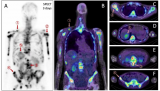

靶向MC1R的Ac-225治疗性核药完成首例患者给药,Alpha-9 Oncology的黑色素瘤诊疗一体化项目取得重要进展

2025年12月4日,临床阶段的放射性药物研发公司Alpha-9 Oncology宣布,已启动一项I期研究,并完成首例患者给药。该研究旨在评估A9-3408的安全性、剂量学及剂量递增情况,这是一种新型靶向黑色素皮质素1受体(MC1R)的Ac-225核素药物,用于治疗经标准疗法治疗后病情进展的MC1R阳性黑色素瘤患者。这一里程碑式的进展推动了Alpha-9的黑色素瘤项目。该项目于去年随着A9-3202的启动而首次进入临床阶段,A9-3202是一种基于Ga-68的显像剂,用于评估MC1R的表... 2025-12-06 核医药放射性药物